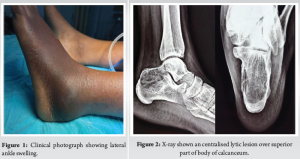

A 27-year-old female presented to OPD with complaints of swelling and tenderness in the lateral aspect of the left ankle and foot for 3 months. There is a history of twisting injury to the left ankle while riding a bicycle 3 months back, after which the patient noticed the swelling. The patient has received conservative management for lateral ankle sprain but, however, no radiographs were taken during such consultations. On clinical examination, there was a diffuse swelling involving the lateral aspect of the left ankle (Fig. 1) which was tender on palpation without any local rise of temperature. There is no history of any constitutional symptoms. Ankle and foot examination are within normal limits. On roentgenography (Fig. 2), we found an expansile, lytic lesion in the proximal aspect of the body of the left calcaneus. The lesion has a narrow zone of transition. There was no periosteal reaction, no matrix, no soft-tissue component. There was no sclerotic margin. Multiple septae appear to be traversing the length of the lesion, producing a trabeculated appearance. Radiologic evaluation of other body parts ruled out multicentric lesions.